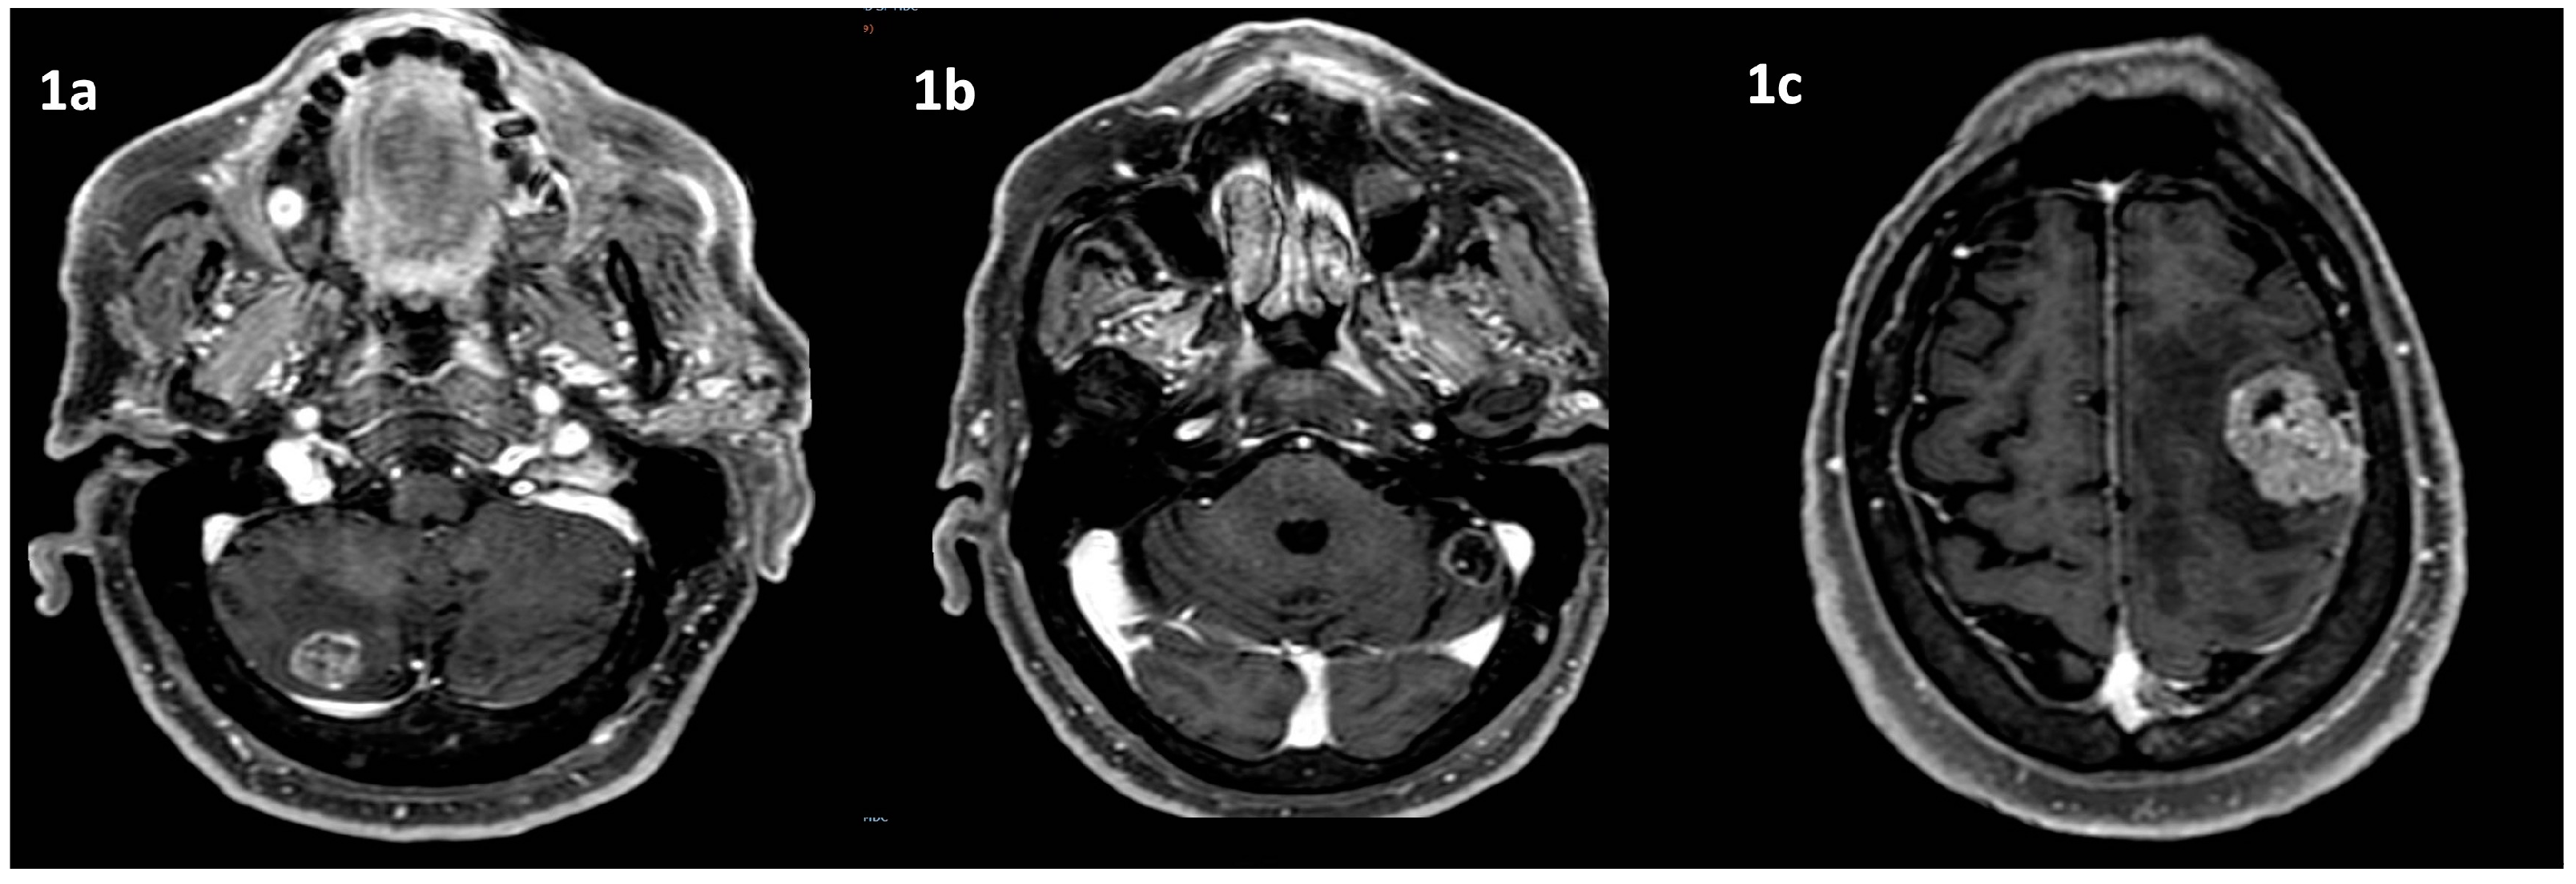

After one week, a total body computed tomography scan (TB CT scan) was performed, revealing a solid nodular, expansive mass (39 mm) in the right upper lobe of the lung and multiple lymphadenopathies in the mediastinum (paratracheal and subcarinal) (Figure 2a).

Fluorodeoxyglucose positron emission tomography (FDG PET) (Figure 2b) confirmed the presence of multiple hyper-capturing lesions consistent with the CT scan findings: right superior lobe (SUV 16.8), mediastinal nodes, plus lesion on the occipital bone. A cT2N2M1c stage IV lung cancer was diagnosed with CEA and Ca19.9 of 15.4 ng/mL (<6) and 65.6 UI/mL (<37), respectively.

Over the following months, regular monitoring with CEA (6.5 ng/ml), Ca19.9 (27UI/mL), CT-PET scans, and brain MRI indicated a complete response 35 months after diagnosis (Figure 5 and Figure 6).

Figure 2. Lung tumor imaging at diagnosis. Legend: (a) lung tumor in the right upper lobe on CT scan; (b) PET-FDG hyper capturing lesion on right superior lobe and mediastinal nodes.

Figure 6. Response to treatment. Legend: (a) CT scan mediastinal and lung complete response to treatments 35 months after diagnosis; (b) PET-FDG complete response to treatments 35 months after diagnosis.